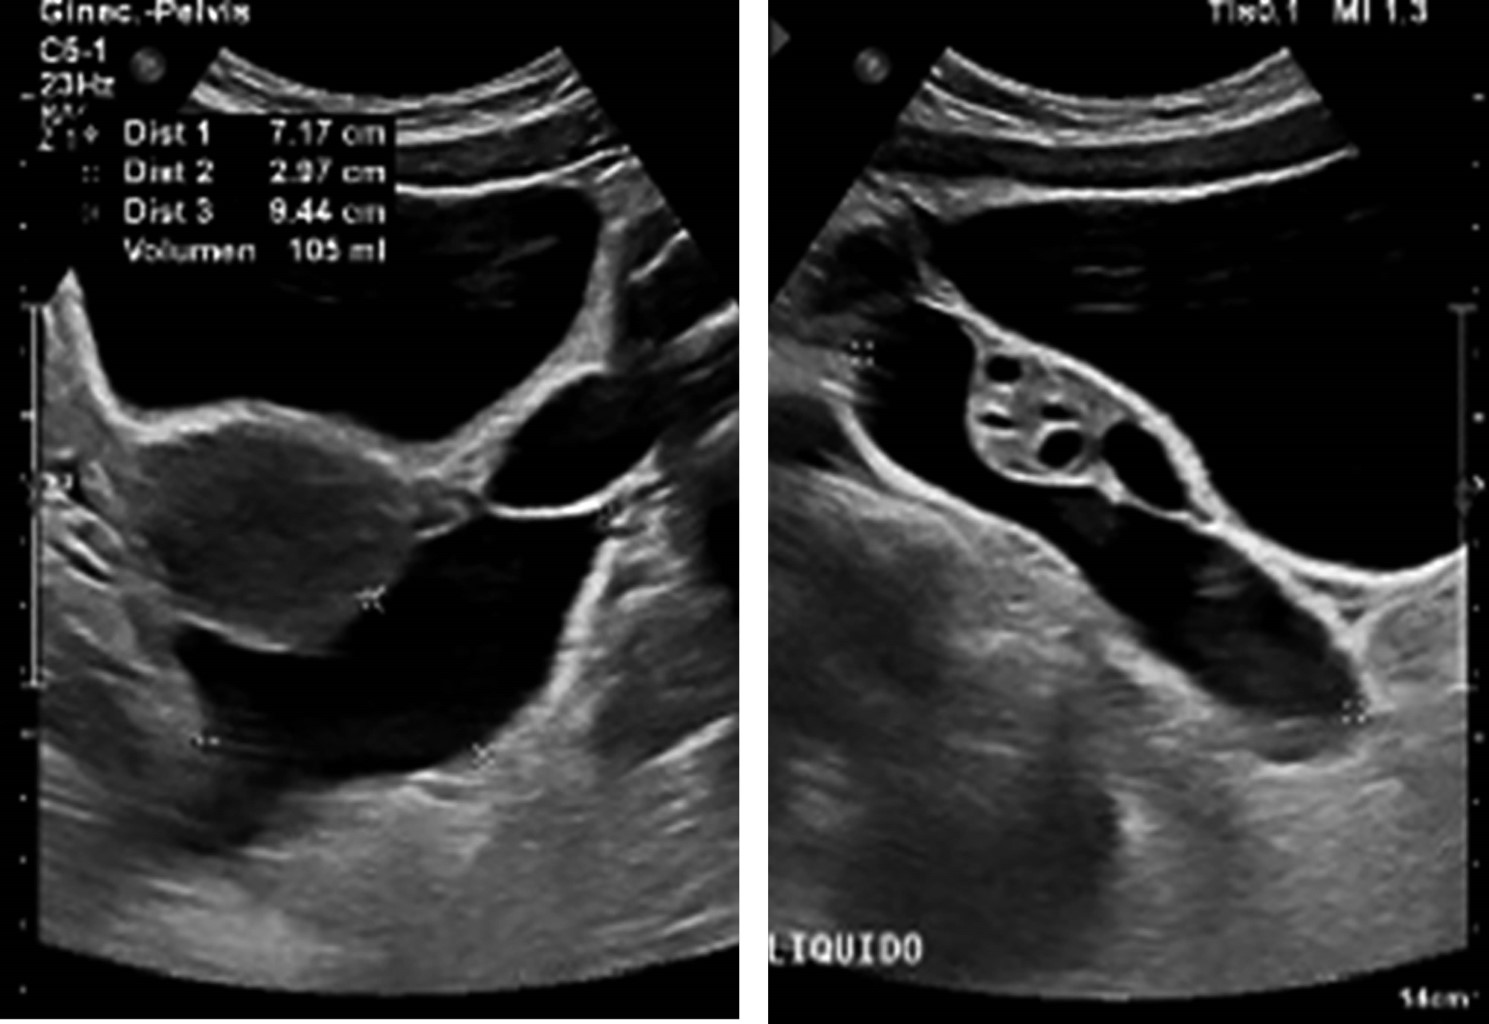

Cita de seguimiento a las tres semanas, con ultrasonido de control, el cual reportó líquido en ambas fosas iliacas y fondo de saco, con presencia de finos septos adyacentes a anexos, comparando con estudio previo se encontró aumento de volumen, resto de órganos pélvicos normales (Figura 1). Se internó por urgencias para complementar su estudio con tomografía axial computarizada de abdomen con contraste intravenoso, reportando abundante líquido libre en hueco pélvico y corredera parietocólica derecha (Figuras 2 y 3). Fue valorada por los servicios de cirugía general y ginecología y obstetricia, programándose para laparoscopía diagnóstica.

La ecografía y la tomografía computarizada (TC) son útiles en el abordaje inicial, revelan masas multiloculadas con tabiques gruesos que desplazan los órganos vecinos sin invadirlos; con todo, estos hallazgos están lejos de ser específicos en MPMB, con sensibilidad entre 15-30%. La resonancia magnética (RM) es el estudio con mayor sensibilidad (99%), mostrando señales hiperintensas que reflejan líquido quístico, con realce de los tabiques. En todas las modalidades de imagen se puede observar líquido libre y engrosamiento peritoneal discreto, en contraste con el mesotelioma peritoneal maligno, que frecuentemente se presenta con ascitis franca y engrosamiento peritoneal difuso.5